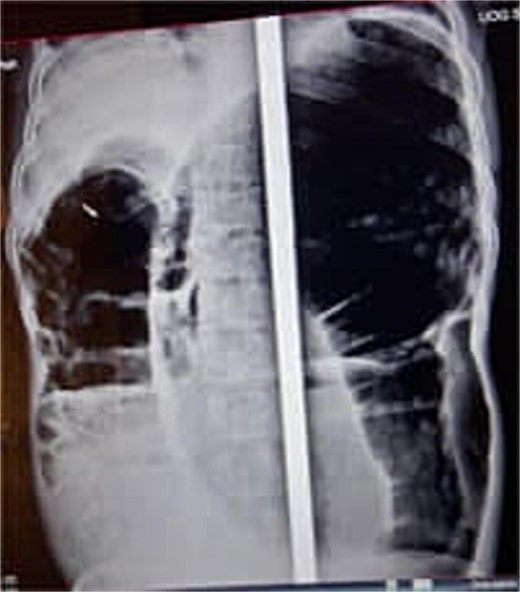

At presentation, his vital signs were stable, but his abdomen was distended, and the rectum was empty upon digital examination. Blood tests revealed hypoalbuminemia (serum albumin of 2.2 g/dL), with normal electrolytes, complete blood count (CBC), and organ function tests. An erect abdominal X-ray showed distended bowel loops with air-fluid levels (Fig. 1). A differential diagnosis of sigmoid volvulus recurrence was considered. However, rectal decompression was unsuccessful. The patient’s condition worsened, with tachycardia (heart rate of 100 bpm), tachypnea (respiratory rate of 24 breaths per minute), fever (37.8°C), and abdominal tenderness. Repeat blood tests showed a left shift in the CBC, raising concerns about peritonitis.

Abdominal X-ray showing dilated colon and multiple air-fluid levels.